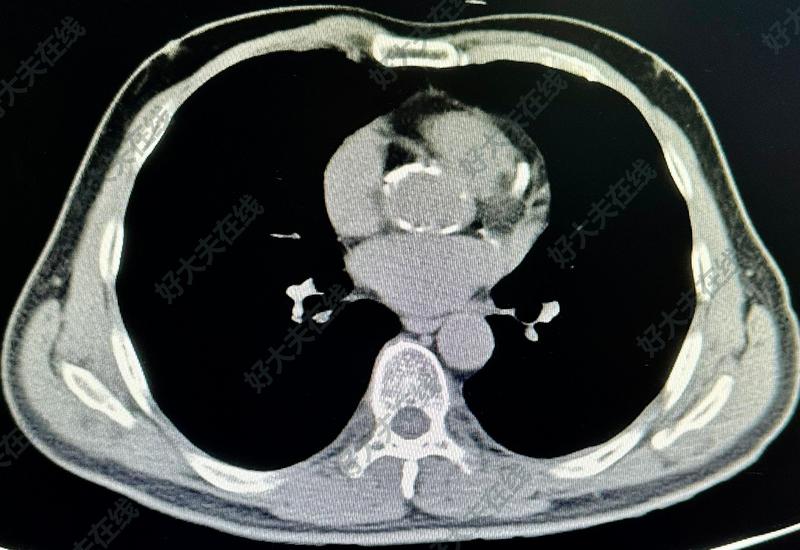

冠脉严重钙化

祖凌云医生的科普号